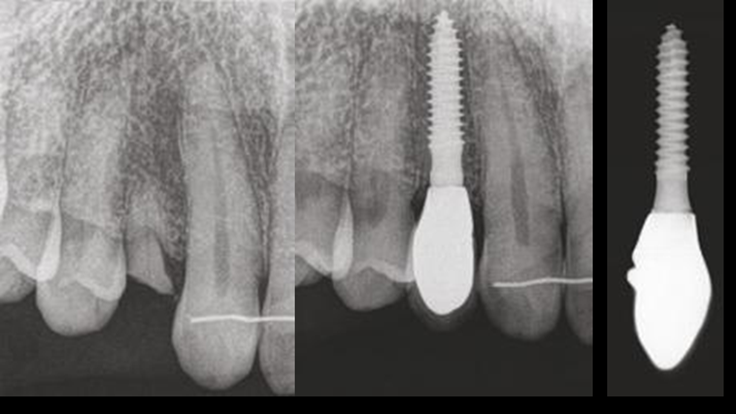

Clinical case: Immediate placement in maxillary anterior narrow space using Advanced Intermezzo

- Courtesy of Dr. Jung Sam Lee, Korea -

Advanced Intermezzo. anterior esthetics, esthetic, provisional restoration, esthetic zone, #13, maxillary anterior, Dr. Jung Sam Lee, anterior aesthetics, aesthetic, aesthetics

Advanced Intermezzo implant system